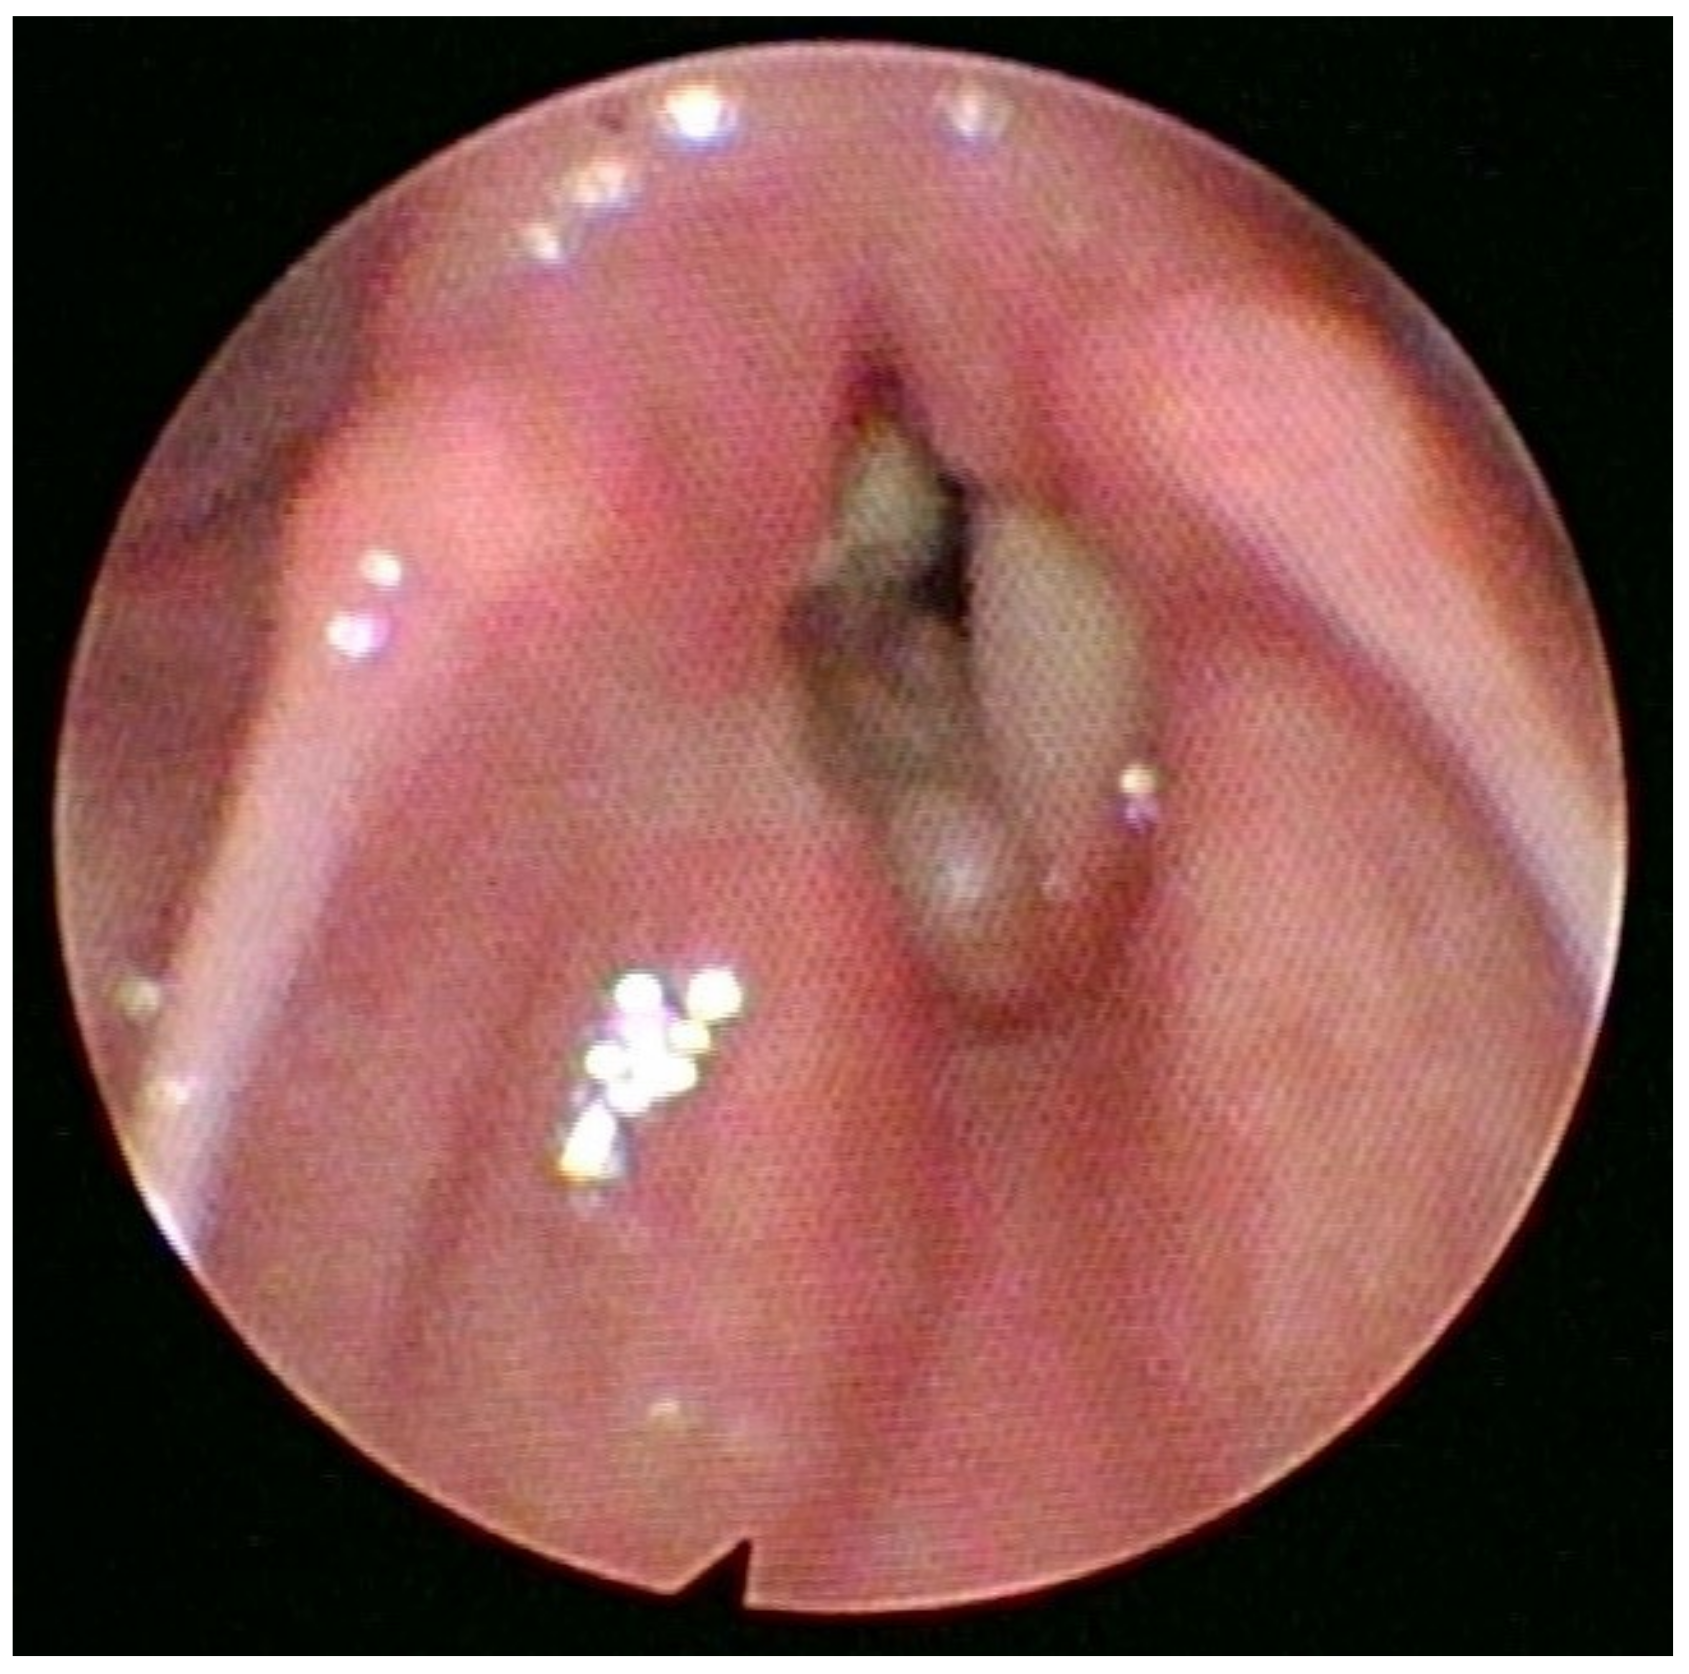

Figure 1.

Endoscopic view of the larynx showing the lesion. The adenoid cystic carcinoma (ACC) arises from the minor salivary glands. It accounts for 1–5% of all head and neck malignancies. Since the minor salivary glands are present in small amounts throughout the larynx, the laryngeal adenoid cystic carcinoma is sporadic, representing less than 1% of all laryngeal malignancies [1]. Regarding the onset of laryngeal ACC (LACC), the prevalent age ranges from 50 to 60 years. However, younger generations can be affected, and both sexes are equally affected, with a slight male predominance and a male-to-female ratio of 1,5:1. There is no evidence connecting LACC etiology with smoking. An early perineural and hematological spread make this kind of carcinoma liable for local recurrence and distant metastasis, especially to the lung. Therefore, is important to increase the frequency of controls during follow-up [2]. Laryngeal ACC can originate from any part of the larynx. The most common origin is the subglottic area (64%), followed by the supraglottic area (25%), the glottic area (5%), and the trans-glottic area (6%) [3,4]. The clinical presentation is usually variable and related to the lesion location [5,6,7]. In November 2021, a 70-year-old no-smoker female patient presented to our hospital’s emergency department with stridor, severe dyspnea at rest, and hoarseness of voice. The O2 saturation level was 87% on air without cyanosis. An endoscopic laryngeal examination revealed bilateral vocal cord paralysis in adduction. Firstly, the patient underwent an urgent tracheostomy under general anesthesia. The procedure also included a laryngeal examination (micro-laryngeal surgery) under general anesthesia with tumor mapping, which revealed a bilateral mucosal thickening of the anterior thirds and anterior commissures of both vocal folds and a right vocal fold submucosal thickening (Figure 1). Multiple biopsies from different laryngeal areas were taken for histopathological examination. The pathological tissue revealed the presence of an adenoid cystic carcinoma of the solid type associated with the immunophenotype CK AE1 AE3 +, CD117+, CK7+/−, p63 +/−, p40+/−, Vimentin +/−, SMA+/−, S100+/−. Then, the patient underwent a CT scan of the neck chest and brain with a contrast medium and an abdominal ultrasound examination. The first chest, brain, and abdominal radiological evaluations did not show metastatic lesions. The neck CT scan revealed the presence of small submucosal bilateral glottic masses, associated with increased cervical lymph nodes volume, without subglottic and extra-laryngeal extensions (Figure 2).